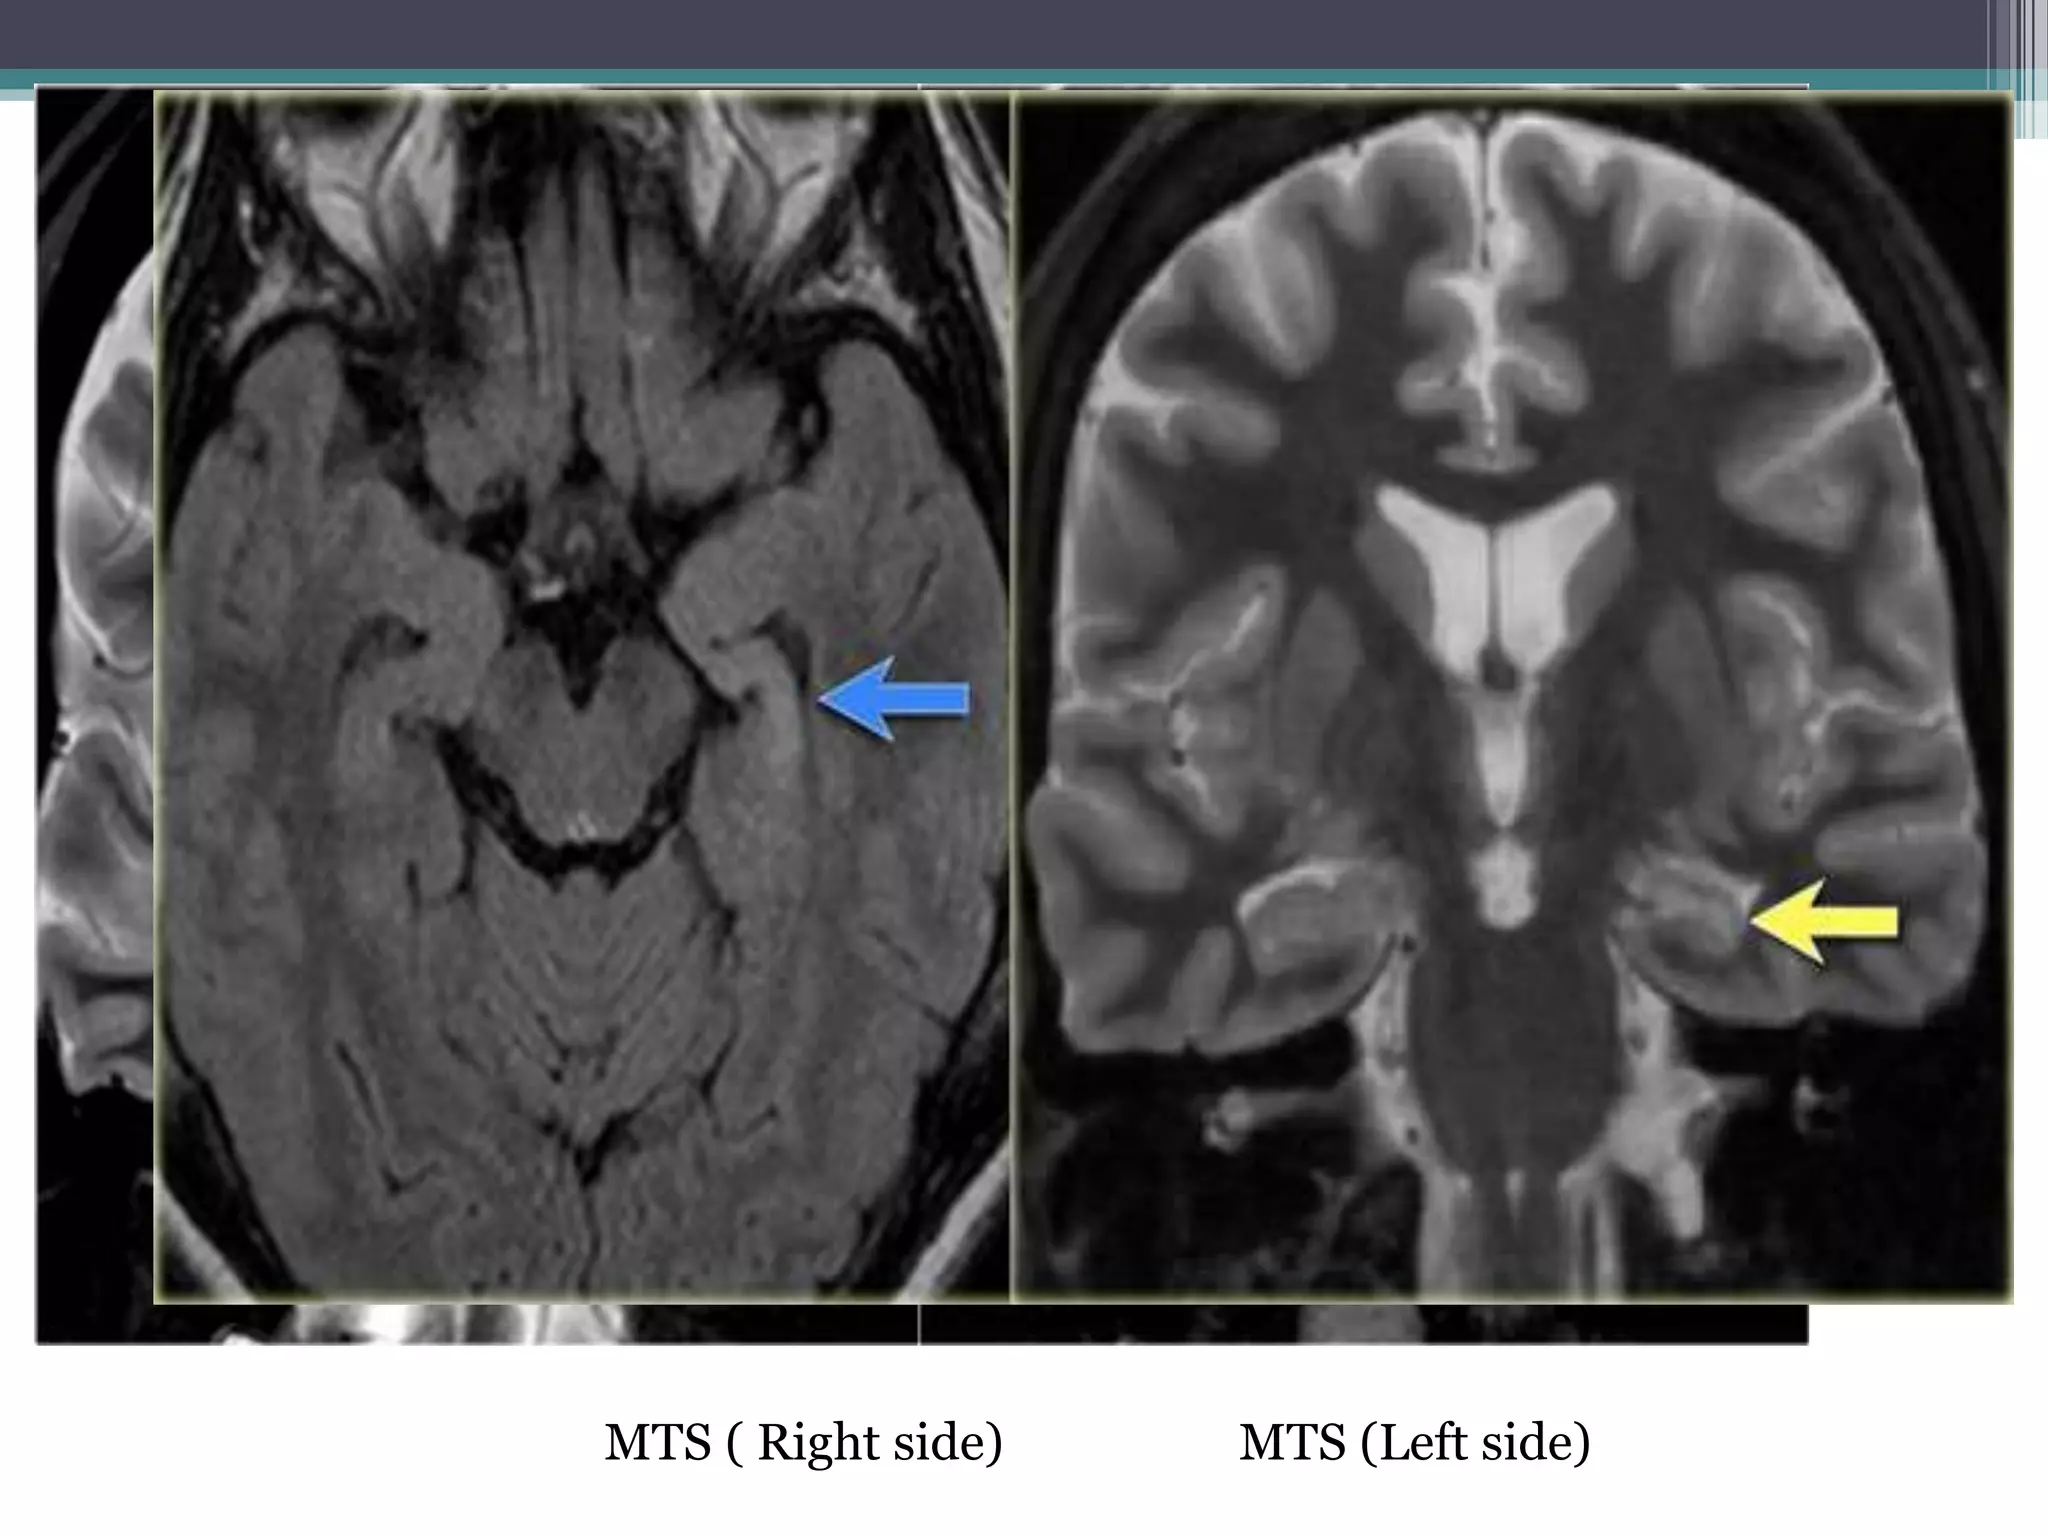

1. Mesial Temporal Sclerosis • Hippocampal Volume loss

• Hippocampal Hyperintensities on

T2/FLAIR ( better on coronal) click

here

MTS ( Right side) MTS (Left side)

MTS ( Rightside) MTS (Left side)